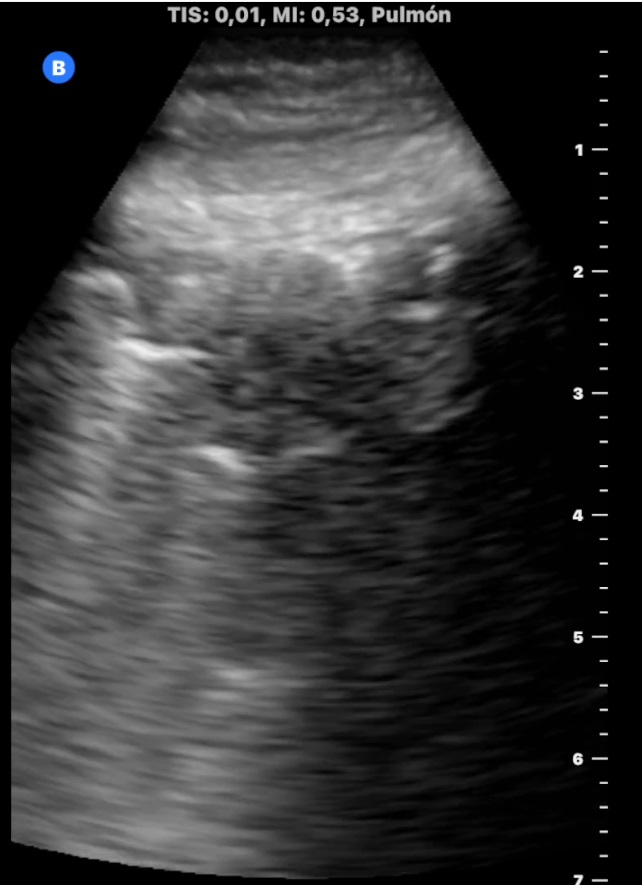

La ecografía pulmonar muestra microconsolidación y líneas B en campo posteroinferior derecho (imagen 1). Ante el antecedente de inmovilización y TEP previo, preguntamos por edemas y refiere inflamación en miembro inferior izquierdo, constatándose cierto aumento de perímetro. La ecografía de MII muestra trombo hiperecogénico femoropoplíteo con captación de Doppler periférico (imagen 2, 3 y 4).

El angioTAC confirma TEP de arteria pulmonar principal derecha. Ingreso en Neumología para vigilancia. Estudio de trombofilia negativo. Anticoagulación indefinida por dos episodios de TVP/TEP.